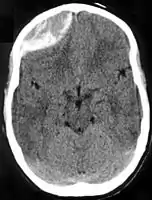

| Epidural hematoma as seen on a CT scan with overlying skull fracture. Note the biconvex shaped collection of blood. There is also bruising with bleeding on the opposite side of the brain. | |

Epidural hematomas usually appear convex in shape because their expansion stops at the skull's sutures, where the dura mater is tightly attached to the skull. Thus, they expand inward toward the brain rather than along the inside of the skull, as occurs in subdural hematomas. Most people also have a skull fracture.[3]

Non-contrast CT scan of a traumatic acute hematoma in the right fronto-temporal area.